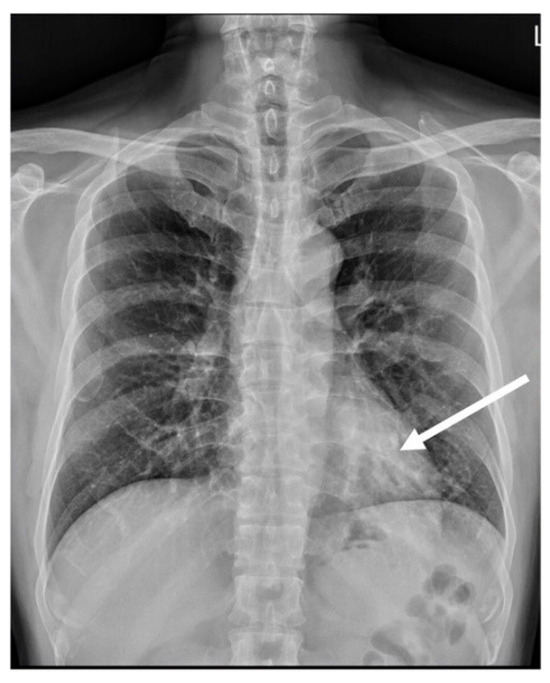

A 51-year-old male patient with no significant medical comorbidities was incidentally discovered to possess a retrocardiac mass after undergoing a chest radiography (Figure 1) during a routine health assessment. Despite the absence of symptoms such as pyrexia, cough, dyspnea, or hemoptysis, the initial impression leaned toward a primary pulmonary neoplasm localized within the left lower lung. Subsequent examinations through CTA (64-slice detector, GE Lightspeed VCT) revealed an enlarged anomalous pulmonary artery originating from the descending thoracic aorta (Figure 2b). Remarkably, the bronchopulmonary distribution within the lung parenchyma remained within normal limits (Figure 2c). As indicated by CTA images, venous drainage returned to the left atrium, and the bronchopulmonary connection was anatomically intact.

Figure 1.

Posteroanterior view of the chest radiograph showed a dilated vessel (arrow), displaying a soft tissue density appearance, mimicking the presence of a mass within the retrocardiac region.